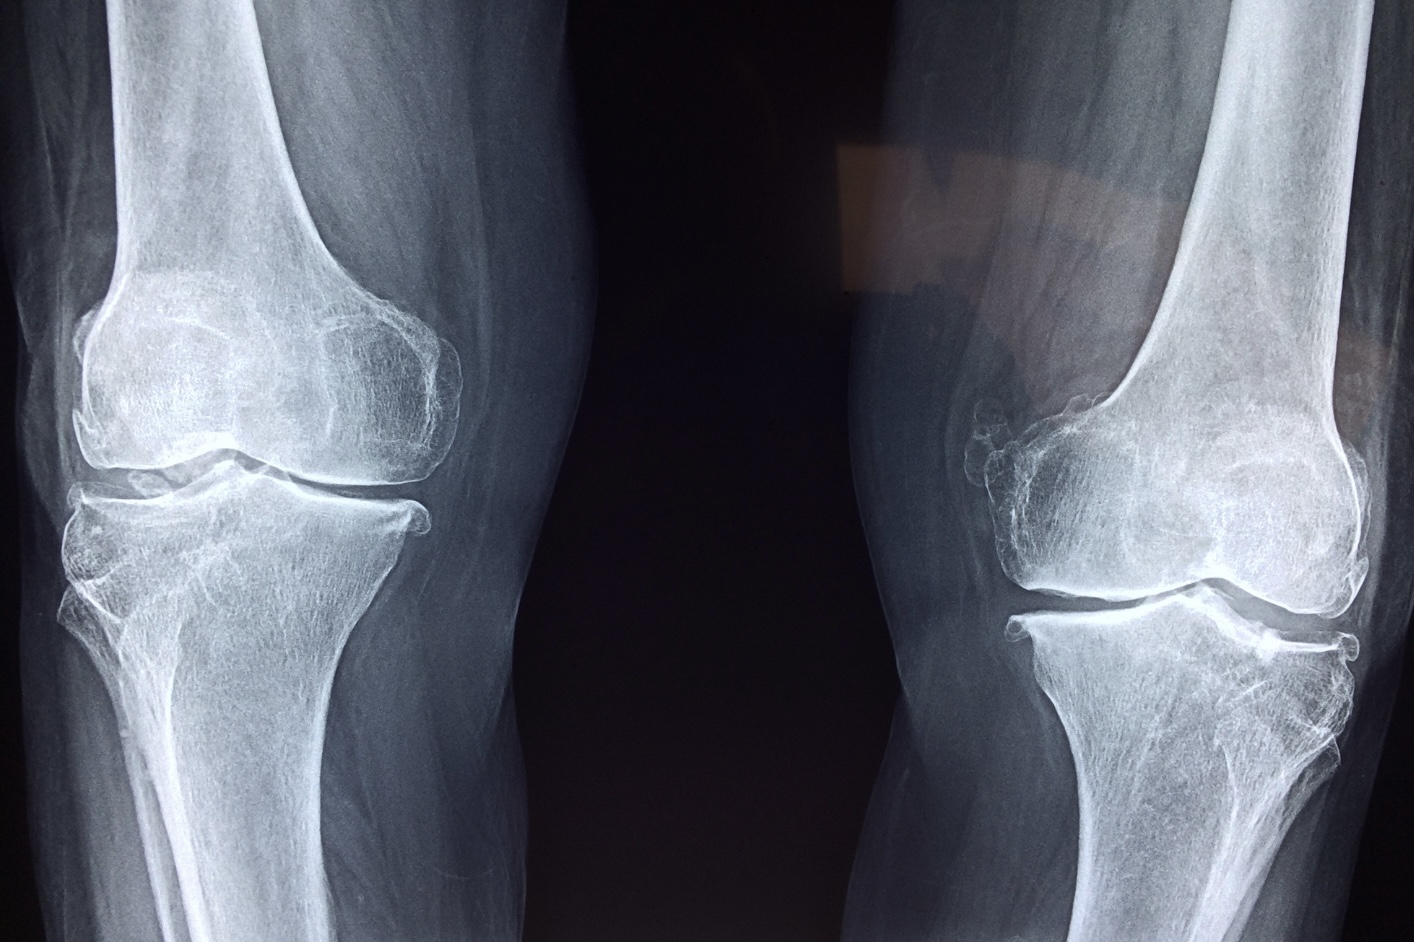

変形性膝関節症は、膝関節の軟骨がすり減ることで炎症や痛みが生じ、関節の変形や可動域制限を引き起こす疾患です。

加齢、体重負荷、筋力低下、アライメント異常などが複合的に関与し、国内では推定1000万人以上が罹患しているとされています。